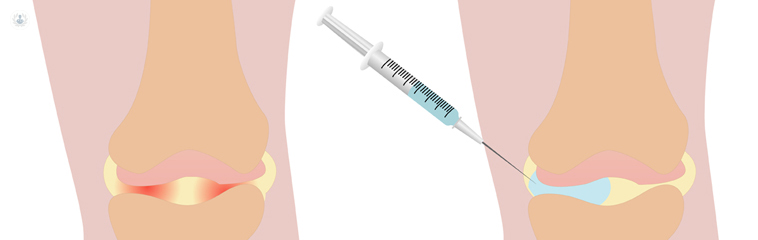

- Infiltraciones articulares y planes de rehabilitación conjunta.